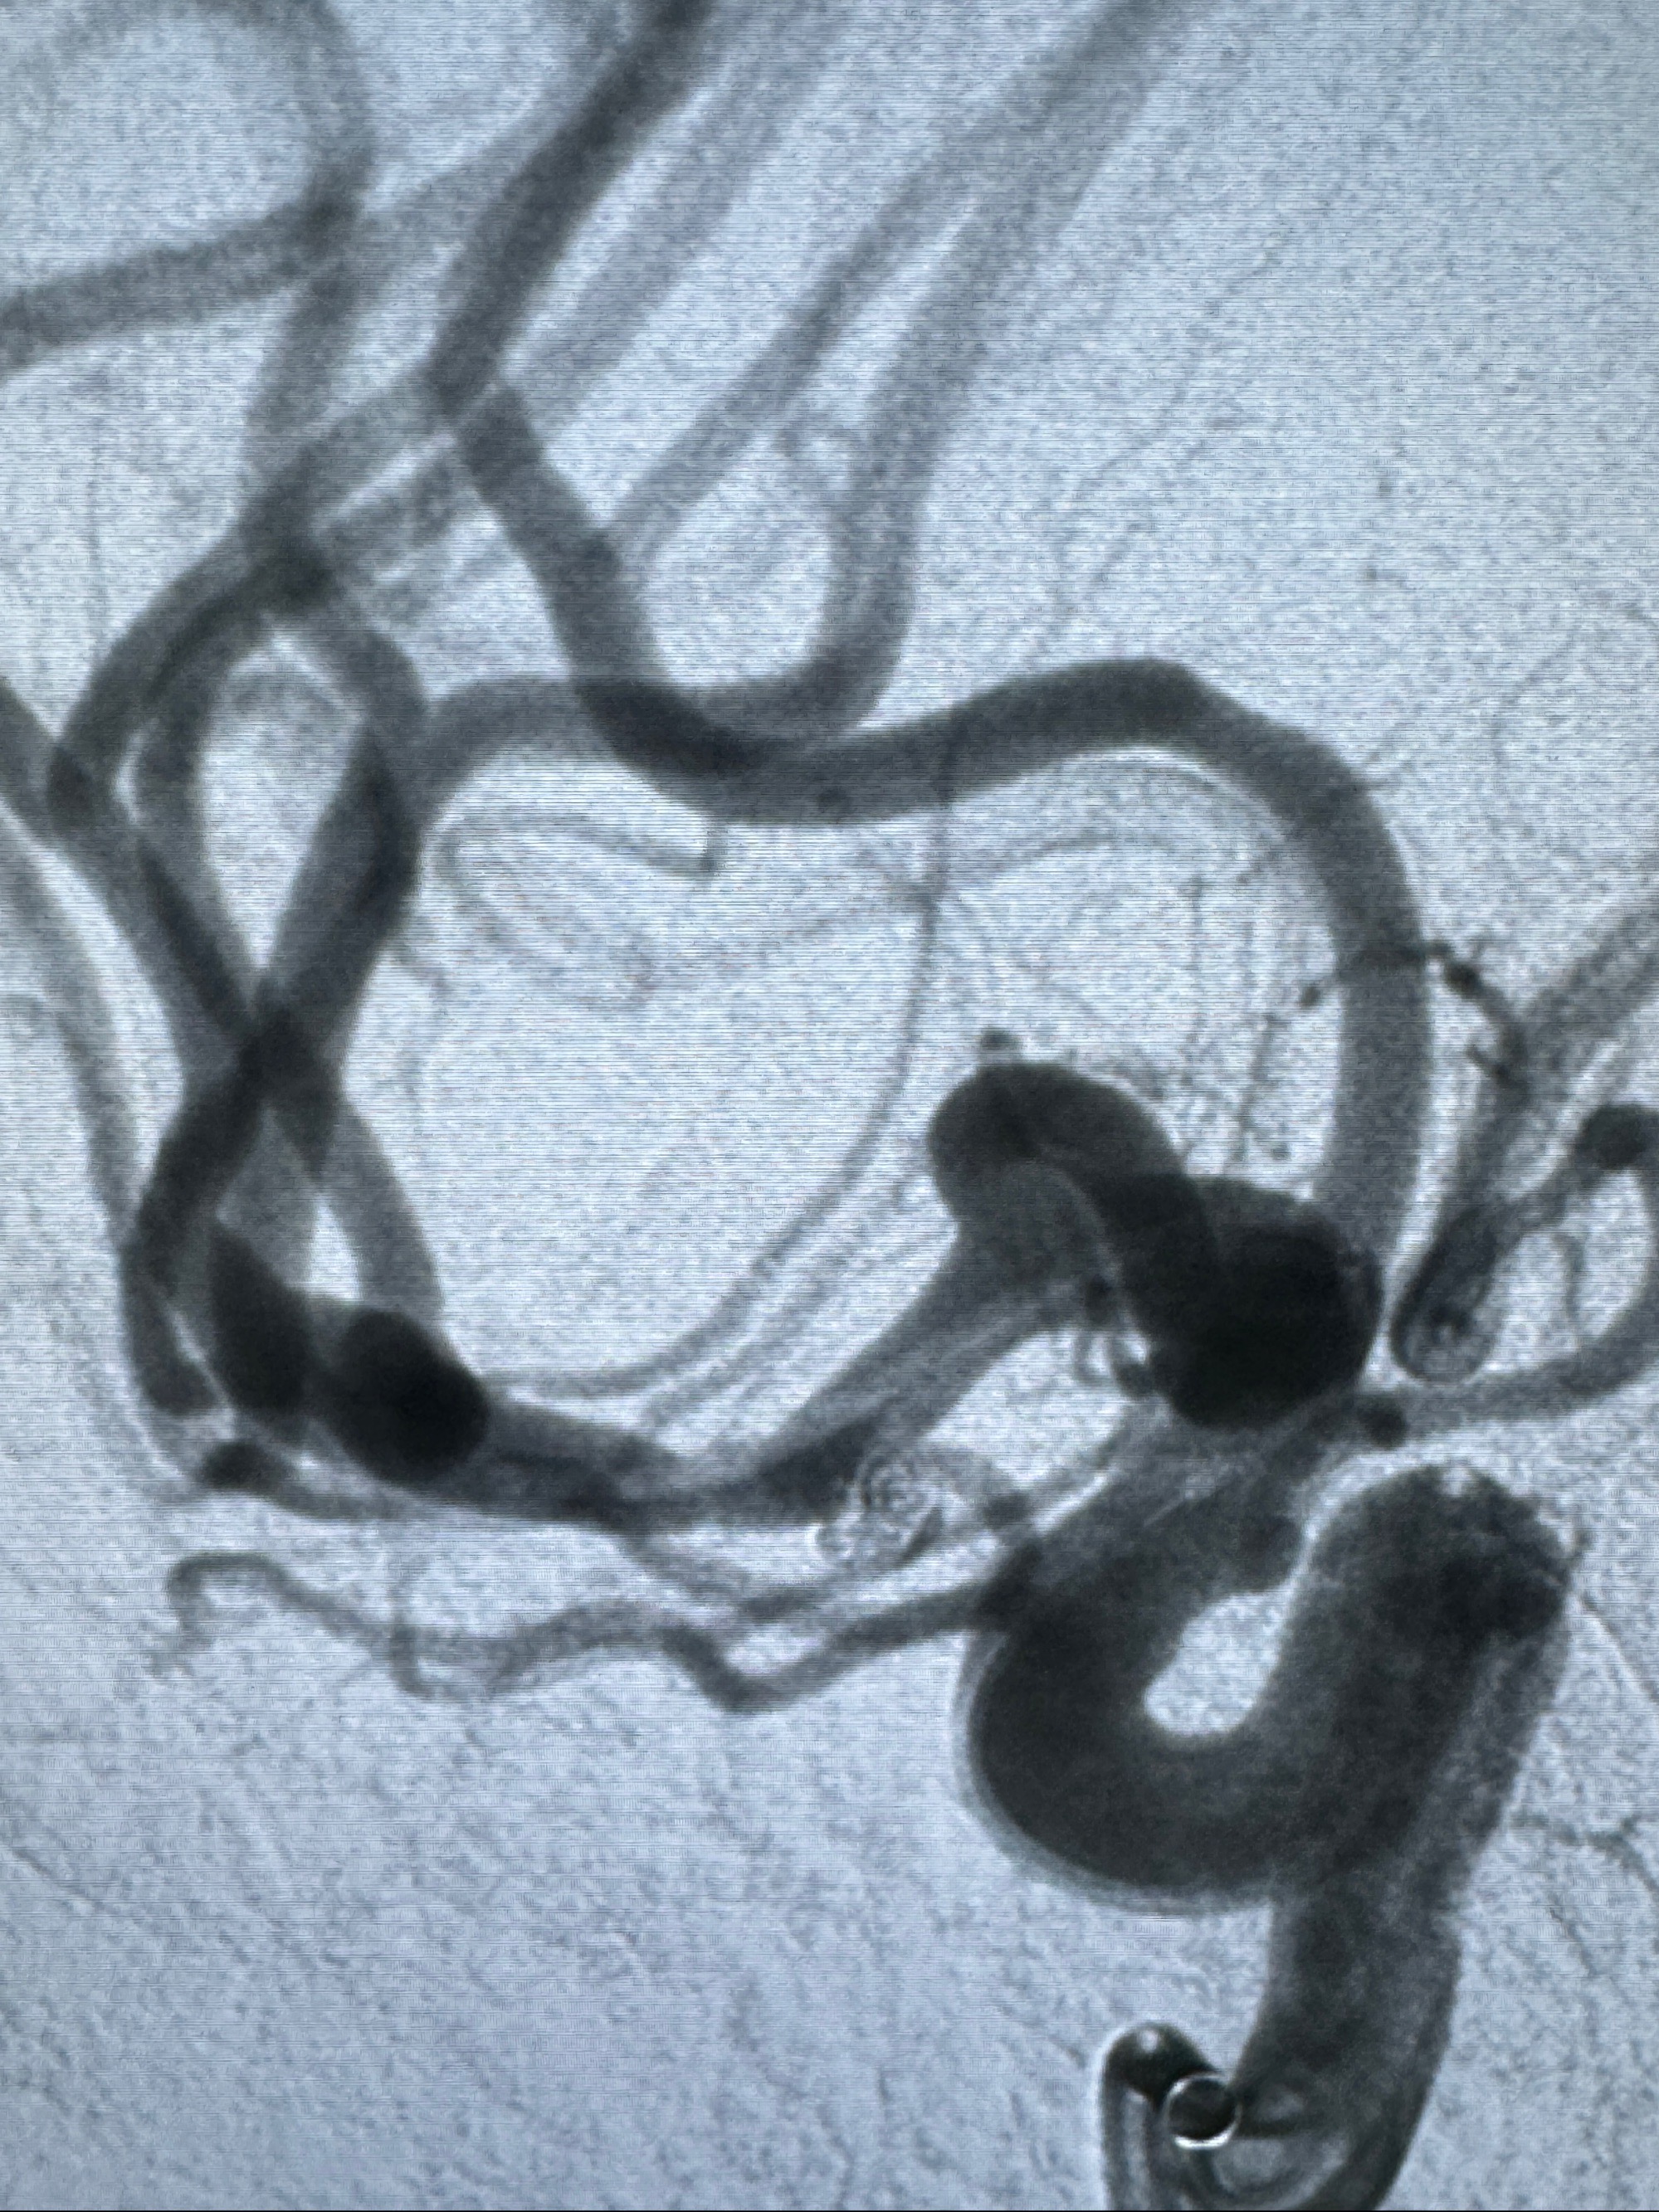

2023-11-24DSA:右侧大脑中动脉下干起始部动脉瘤,约2.3*2.5mm,形态规则

2023-12-04全麻下行支架辅助治疗

S-AB4-20mm